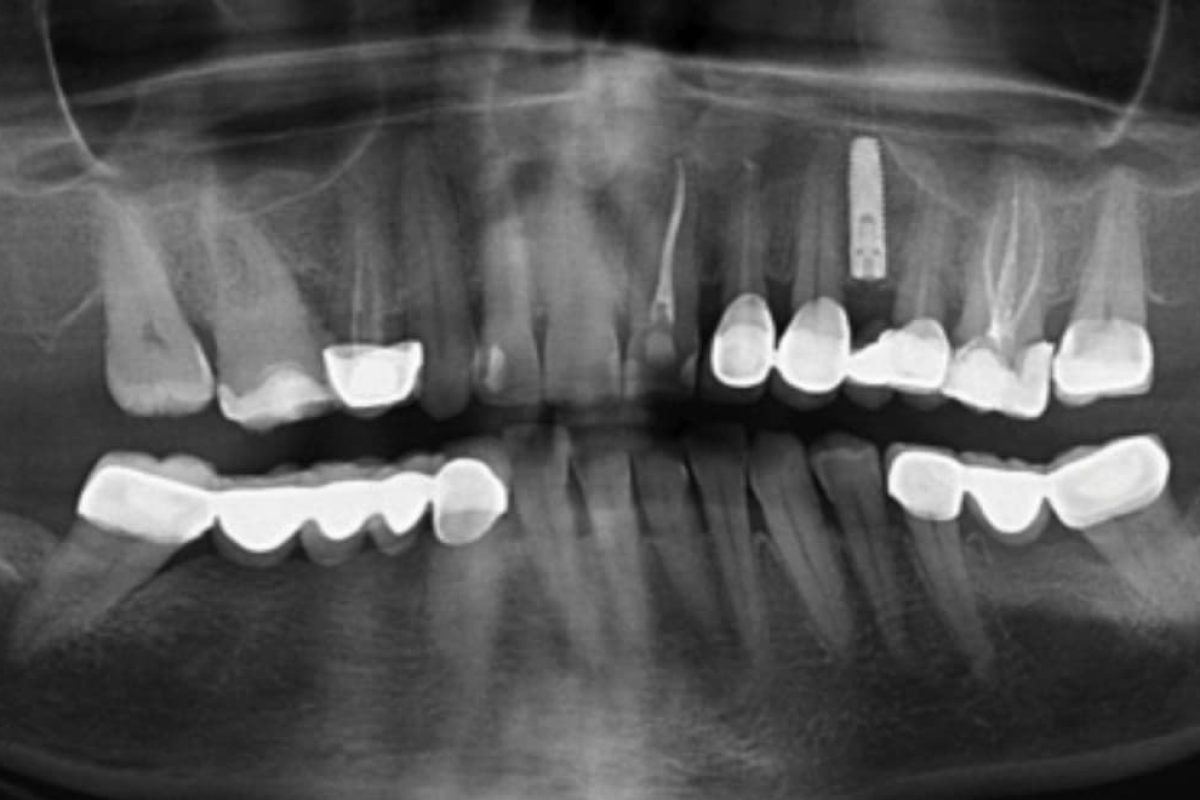

İmplantın yerleştirilmesi ve sol maksillada oldukça eksik diş setinde bovin kemiğinin eş zamanlı olarak büyütülmesi bir hasta vakası olarak sunulmaktadır. Diş setinin daralmış yatay boyutlarına rağmen, standart olarak 3.75 mm çapındaki bir implant kullanılmıştır. İmplant kret altından yerleştirilmiştir ve iyileşme süresi yaklaşık bir aydır. Toplamda 2.5 ay süren tedavi süresi tatmin edici bir estetik ve işlevsel sonuca yol açmıştır.